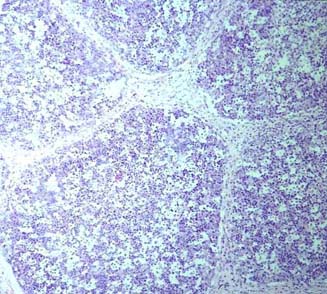

| DEPLECION PEYER: Folículos linfoides de una placa de Peyer en el que se observa hipocelularidad con presencia de restos celulares en los espacios libre. |